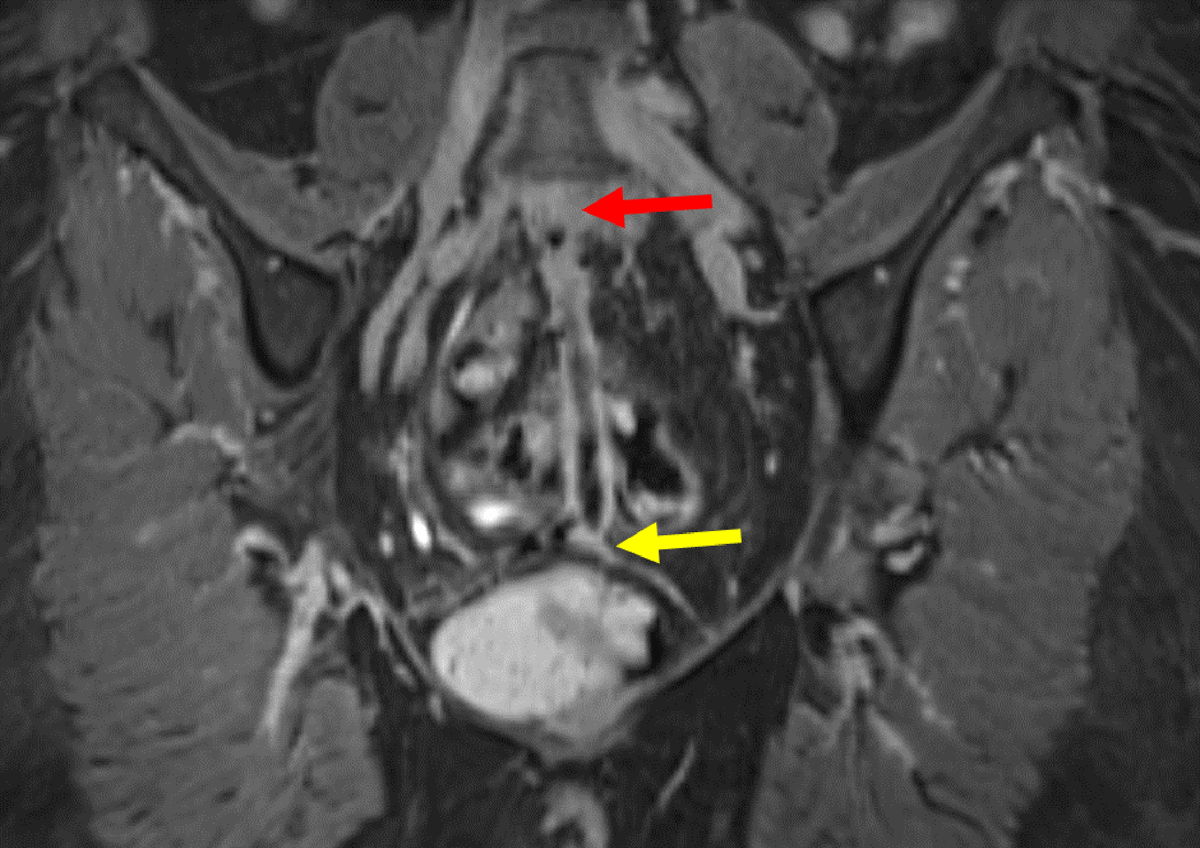

Figure 7

Sagittal contrast MRI in T1 fat saturation weighing: Full path of fistula from L5-S1 (yellow arrow) to the vagina. The fistula (red arrow) presents with a hyperintense wall surrounding a hypointense lumen.